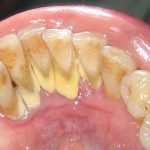

Khá nhiều người chủ quan trong việc chăm sóc răng miệng và cho rằng chỉ cần chải răng đều đặn hằng ngày là đã đảm bảo vệ sinh răng miệng một cách toàn diện. Đó là quan niệm sai lầm vì vi khuẩn hoạt động và diễn tiến trong môi trường răng miệng chúng ta không thể kiểm soát được. Lấy cao răng định kỳ là một biện pháp để phòng tránh các bệnh lý về răng miệng một cách hiệu quả.

Theo các bác sĩ nha khoa khuyến cao, mỗi chúng ta nên định kỳ lấy cao răng từ 3-6 tháng/lần mới có thể làm sạch được các mảng bám lâu ngày ở răng. Khi mảng bám này tồn đọng trên răng lâu ngày thì chải răng thường xuyên cũng không thể làm sạch được.

Sử dụng công nghệ EMS sẽ đi sâu vào tận khoang nha chu có độ sâu 10mm nên nó sẽ lấy đi toàn bộ vi khuẩn và các mảng bám tích tụ lâu ngày trên răng. Nếu không lấy sạch các mảng bám này thì đó là nguyên nhân gây nên bệnh viêm nha chu hoặc các bệnh sâu răng, viêm lợi…